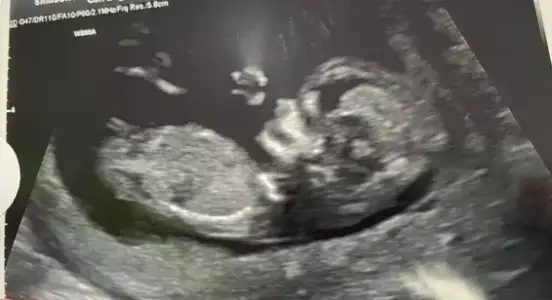

Cınsıyet zamanı patladım12+6 çıktı arayı açmıştı 4-5gün azcık kapamış 1 gün önde görünüyor. Kızzzzz noldu senin meşhur sabrınainsan ilerledikçe merak ediyor ama yaaa. Bakıyomuşsun bizim bütün grup kız

Yaa demeyın oyle heyecanlanıyorummKızlaaaarrrr bugün tarama için perinatolojideydimm ve bu doktor da cinsiyeti kız gördü12+4

Birkaç hafta sonra kesinleşir ama ikisi de aynı görünce galiba az çok belli diye düşünüyorum![]()

Bu arada asıl bomba yükselik ihtimalle kız dedi.![]()

Ayyy çok sevindim canım sende kız istiyordun sanırım darısı da bizlere inşallahKızlaaaarrrr bugün tarama için perinatolojideydimm ve bu doktor da cinsiyeti kız gördü12+4

Hayırlı olsun. Gülüşü görünüyormu ya 3 ayda :)Evet canım bizim grup %90 kızcıydı en son.

Ah amin inşallahh. Bir de gülüyor usg de Allahım eridim![]()